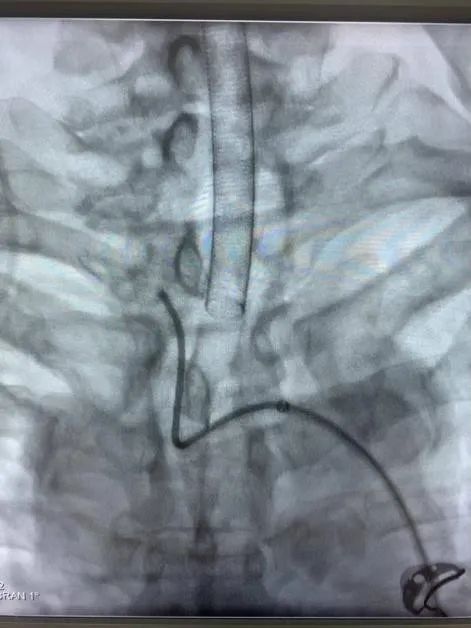

近日,省人民醫(yī)院神經(jīng)外科為一位高齡動脈瘤患者施行了介入治療,成功栓塞了破裂的大腦中動脈瘤?;颊咭蛲话l(fā)暈厥后頭痛不適入院,急診行顱腦CT檢查提示蛛網(wǎng)膜下腔出血,行顱腦CTA檢查后證實患者存在右側(cè)大腦中動脈瘤?;颊吒啐g,既往基礎(chǔ)病多,高血壓病、糖尿病、冠心病、雙側(cè)頸動脈硬化、雙側(cè)腹股溝疝術(shù)后等,手術(shù)風(fēng)險較大,經(jīng)家屬簽字同意后,當(dāng)日急診全麻下行“右側(cè)大腦中動脈瘤介入栓塞術(shù)”,術(shù)中見血管迂曲明顯,導(dǎo)管到位艱難,經(jīng)過努力,手術(shù)順利結(jié)束。術(shù)后予多次腰椎穿刺術(shù)釋放血性腦脊液,患者頭痛頭暈癥狀漸緩解?;颊咦≡褐委?/span>10天后順利康復(fù)出院,未留后遺癥。